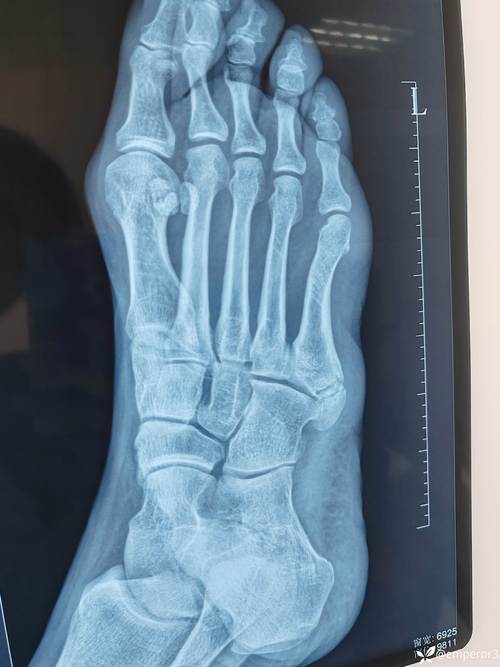

- X线片:是首选的检查方法,可以清晰显示骨骼形态,判断是否存在骨折、骨折类型、骨骺损伤、骨软骨瘤等。

(图4示意:儿童第五跖骨基底骨折的X线片示意图,标注骨折线;图5示意:骨软骨瘤的X线/CT示意图,显示菜花状骨性突起)